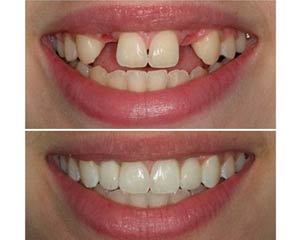

ایمپلنت